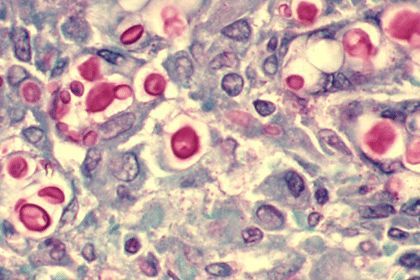

肺隐球菌病为新型隐球菌感染引起的亚急性或慢性内脏真菌病。主要侵犯肺和中枢神经系统,本菌感染后仅引起轻度炎症反应。 会有低热、咳嗽、胸痛等症状。

果然不出意料,郑先生血液和肺穿刺组织块的新型隐球菌荚膜抗原阳性,肺泡灌洗液也找到隐球菌。